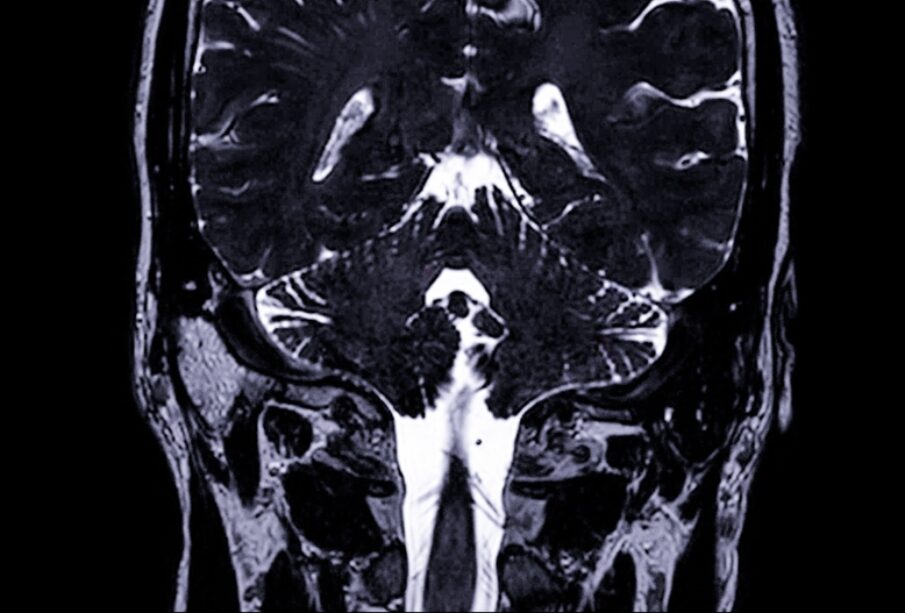

Akustinės neuromos diagnozę gali apsunkinti tai, kad simptomai dažnai panašūs į kitų vidinės ausies ligų požymius, ypač kai navikas mažas. Tiksliam įvertinimui naudojami keli tyrimai:

- klausos tyrimas (audiograma)

- kompiuterinė tomografija (KT)

- magnetinio rezonanso tomografija (MRT)

MRT tyrimas laikomas tiksliausiu, ypač kai naudojama kontrastinė medžiaga. Maži navikai (nuo 2 mm dydžio) dažniausiai aptinkami šio tyrimo metu. KT tyrimu dažniausiai nustatomi bent 2 cm dydžio navikai.